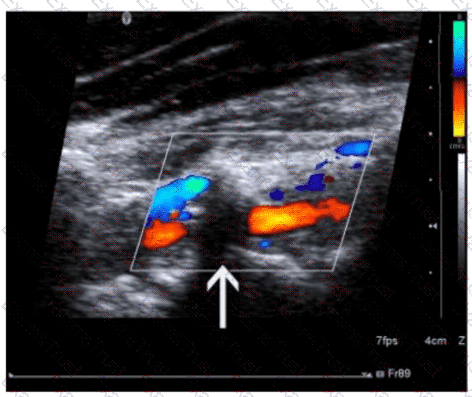

Question 31

Which pulsed-wave Doppler adjustment would be appropriate to correct the aliasing seen in this image?

Options:

A.

Increase the spectral Doppler gain.

B.

Decrease the spectral Doppler gain.

C.

Increase the Doppler pulse repetition frequency.

D.

Decrease the Doppler pulse repetition frequency.